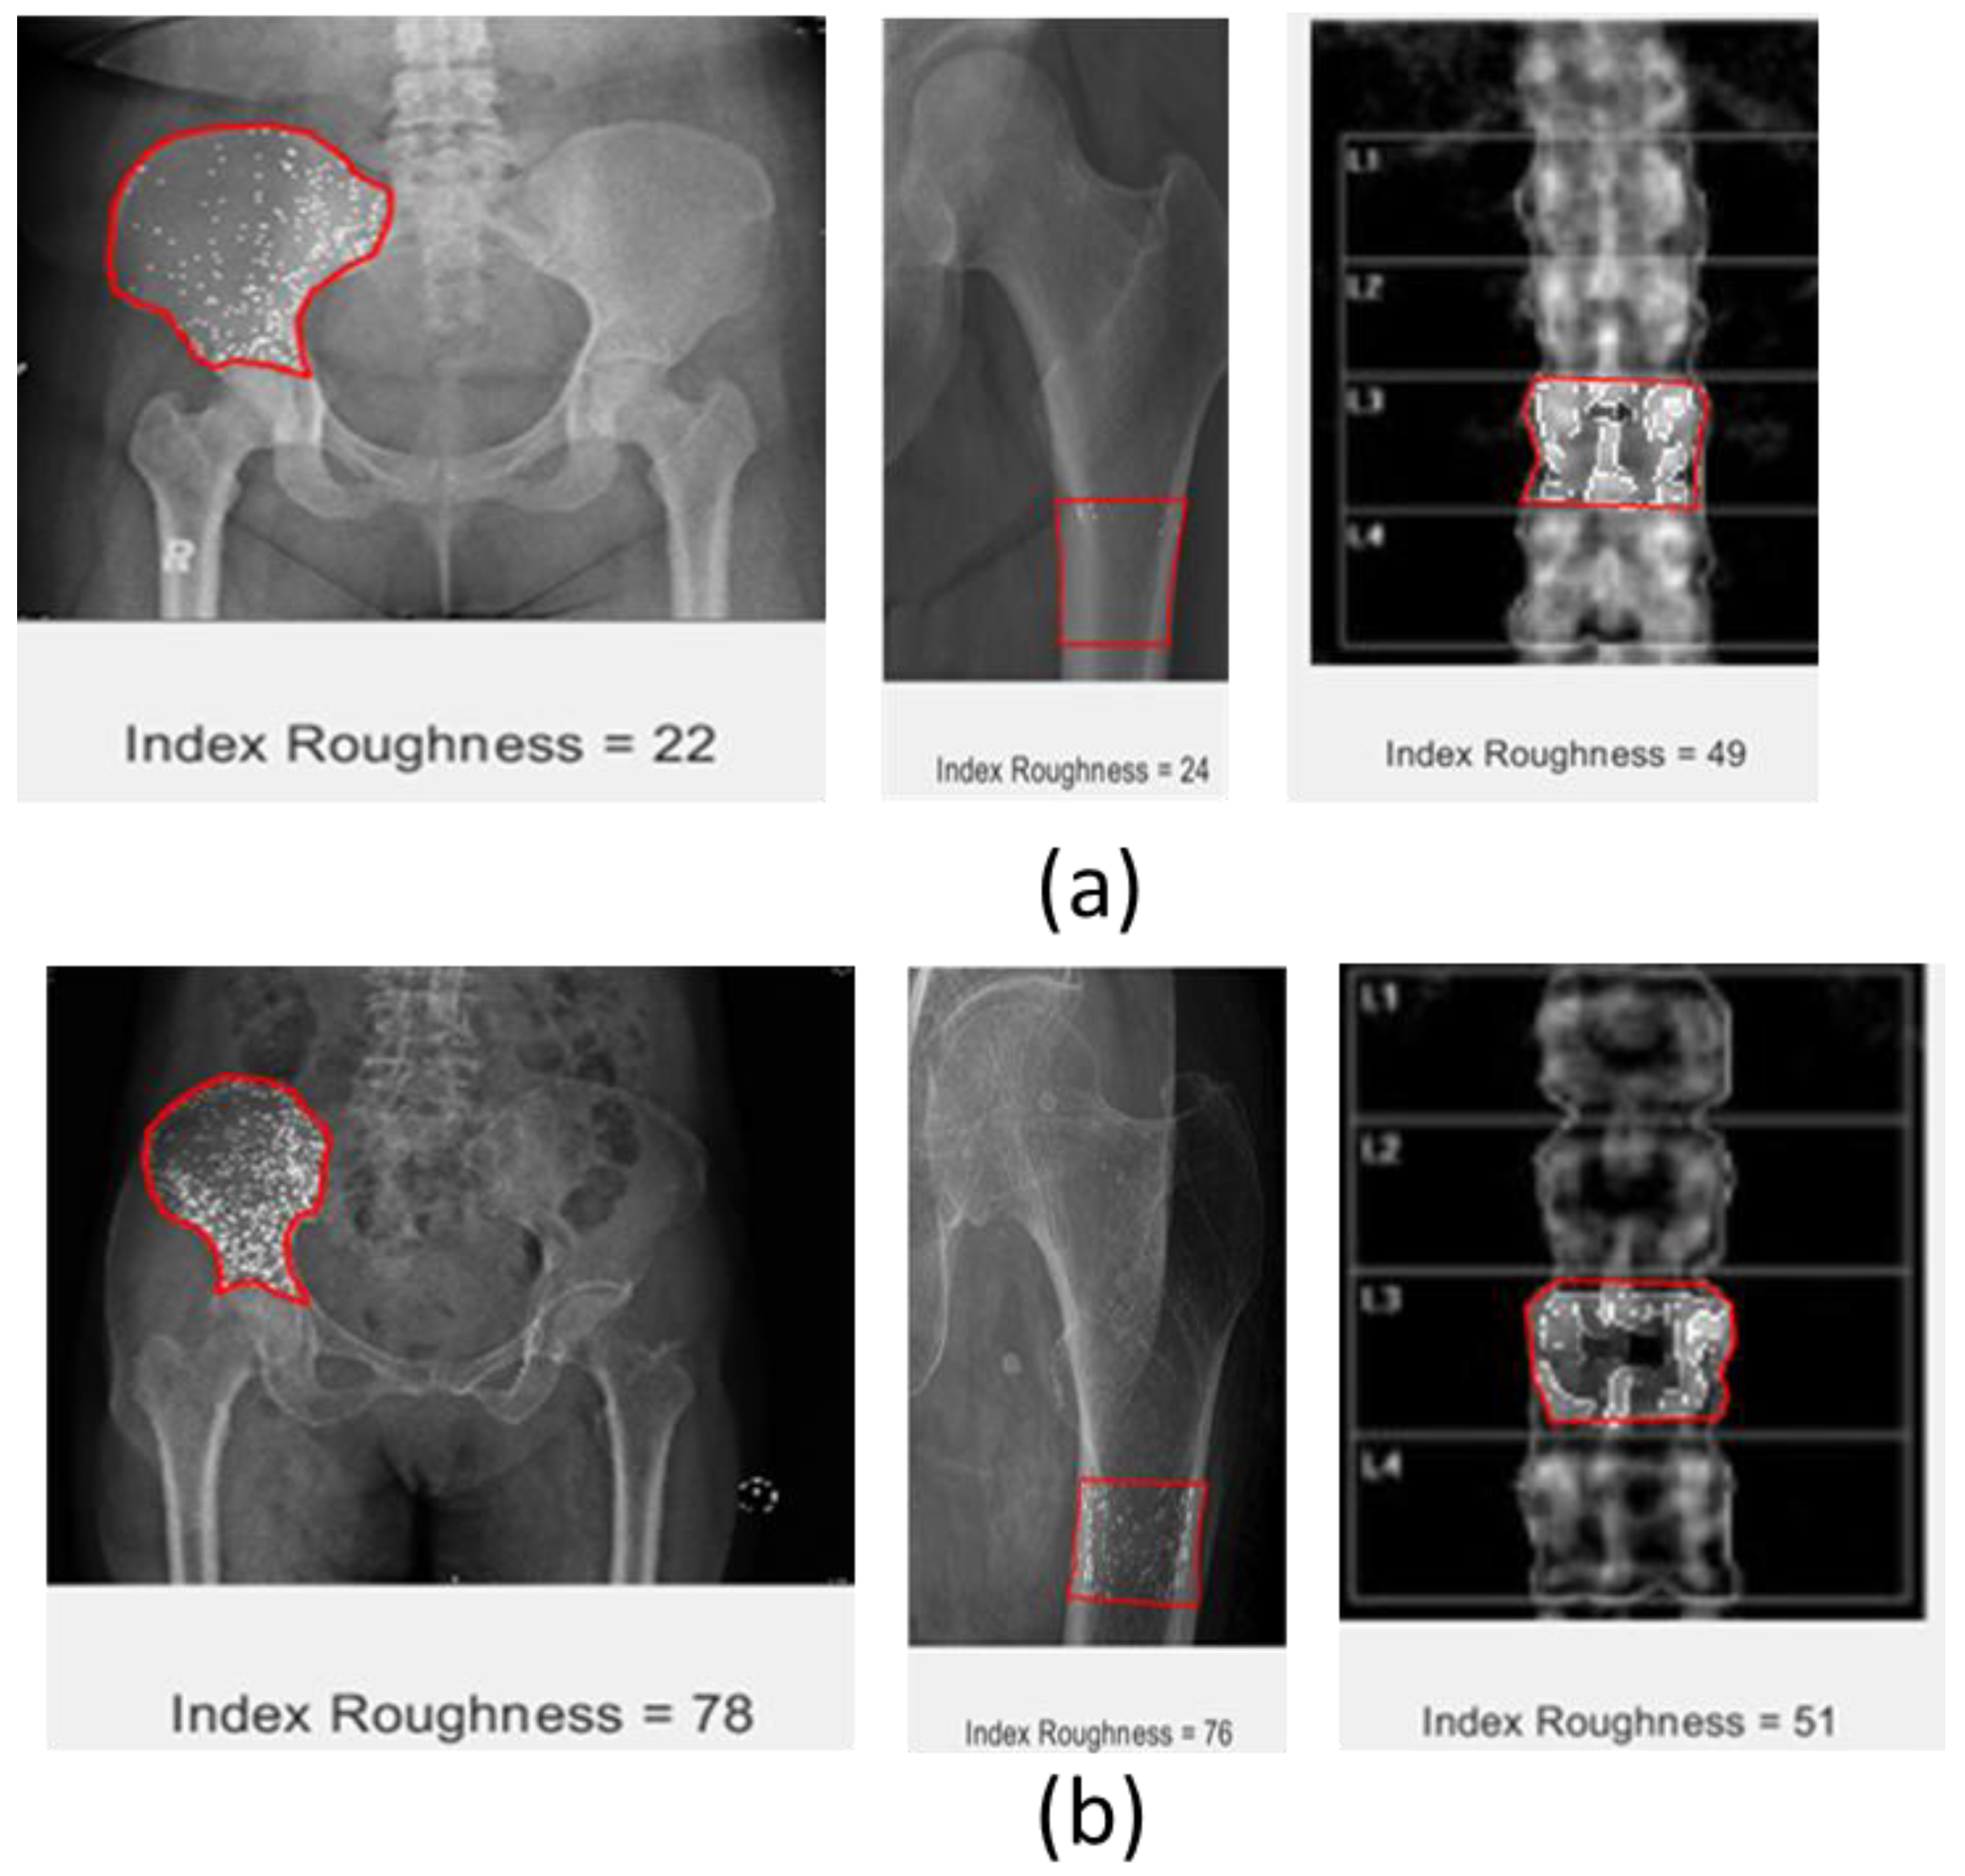

5.3. Roughness Index

The roughness attribute is calculated by subtracting the intensity of each pixel from the average value of intensity for the whole image. The roughness index is then calculated as the total value divided by the total number of pixels inside the ROI. The roughness index consistently indicated a significant increment from normal to osteoporosis on all scanning modalities in both CT scans and DEXA images, where the roughness index of osteoporosis is higher than normal bone. The visual image of roughness also indicates the significant difference between normal and osteoporotic bone, as bone with osteoporosis is visualized with a prominent white spot and normal bone with a less dominant white spot. Looking at this visual, it will also be easier to differentiate normal bone from osteoporotic bone. A summary of the roughness attribute applied to the ROI for each data set is shown in Figure 5.

Figure 5. Roughness index of different image data of pelvic (left), hip (middle), and lumbar spine (right); (a) normal bone and (b) osteoporotic bone, red box indicate a selected ROI.